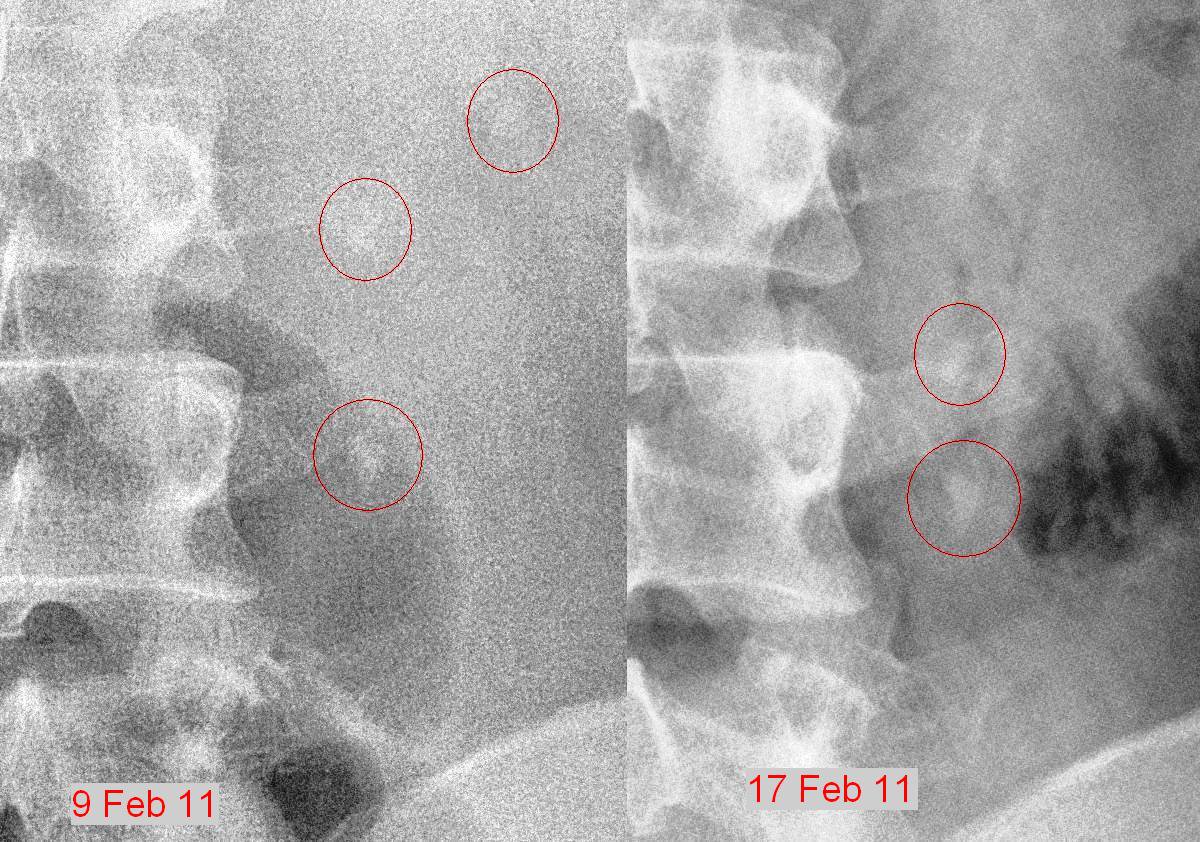

The uncertainty affected me, since a total blockage would cause a back flow of the urine, thereby affecting my left kidney. I consulted the urologists in UKMMC and they told me to get CT urogram done. I managed to get a CT scan done on the very next day on the 18th Feb.

You can clearly see the stones in the CT scan film. Can you see it? Hint – the two white spots in the middle of the picture.

The CT scan report indicated that I had 2 humongous stones (9 and 8 mm in diameter). There was no way that these stones could come out through the urethra since they won’t fit through the urethra nor the urethral opening. The UKMMC urologists suggested laser pulverization of the stones and removal via urethroscopy.